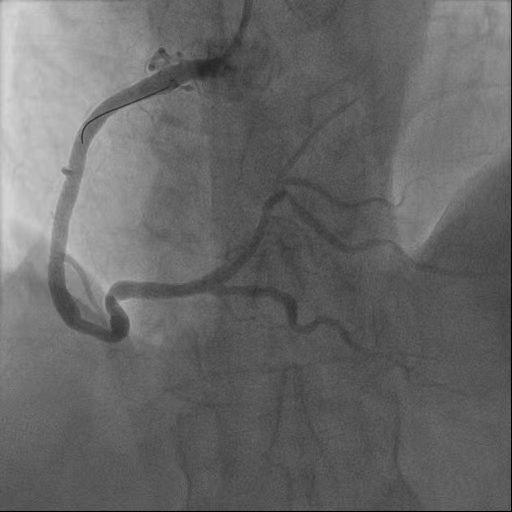

经过胸痛中心绿色通道,综合内科主任蔡国才带领的介入团队通过穿刺右侧桡动脉,将纤细的造影导管送入血管到达冠状动脉开口。屏幕上清晰显示:前降支中段一处99%的狭窄正在“作祟”——这正是导致老人胸痛的“罪魁祸首”。

(左:术前 右:术后)

经过团队的精准操作,医护配合,迅速将导丝通过狭窄病变,沿着导丝送入球囊导管,从患者进入医院大门到导丝通过仅仅过去32分钟(D-to-W),狭窄的冠状动脉血管被成功扩张,并顺利植入支架,冠脉狭窄血管处的血流瞬间恢复正常。刘婆婆胸痛症状完全缓解,生命体征平稳,手术结束,家属激动地握住医护人员的手,连声道谢。